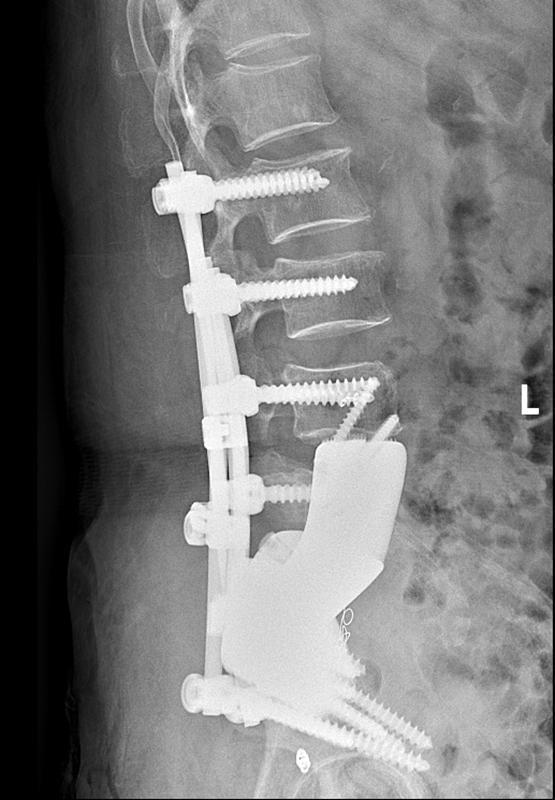

术后腰椎侧位X线。

为尽最大勤恳秩序肿瘤、保留肢体功能,熊女士住院后,贵医附院骨肿瘤休养组为其进行了3D打印个体化肿瘤假体谋略,并于2024年12月收效扩充“全骶骨+半骨盆+L5椎体矢状位切除+3D打印肿瘤假体置换”手术,这亦然贵州首例“半骶骨+半骨盆+L5椎体一期切除鸠合3D打印肿瘤假体置换”病例。